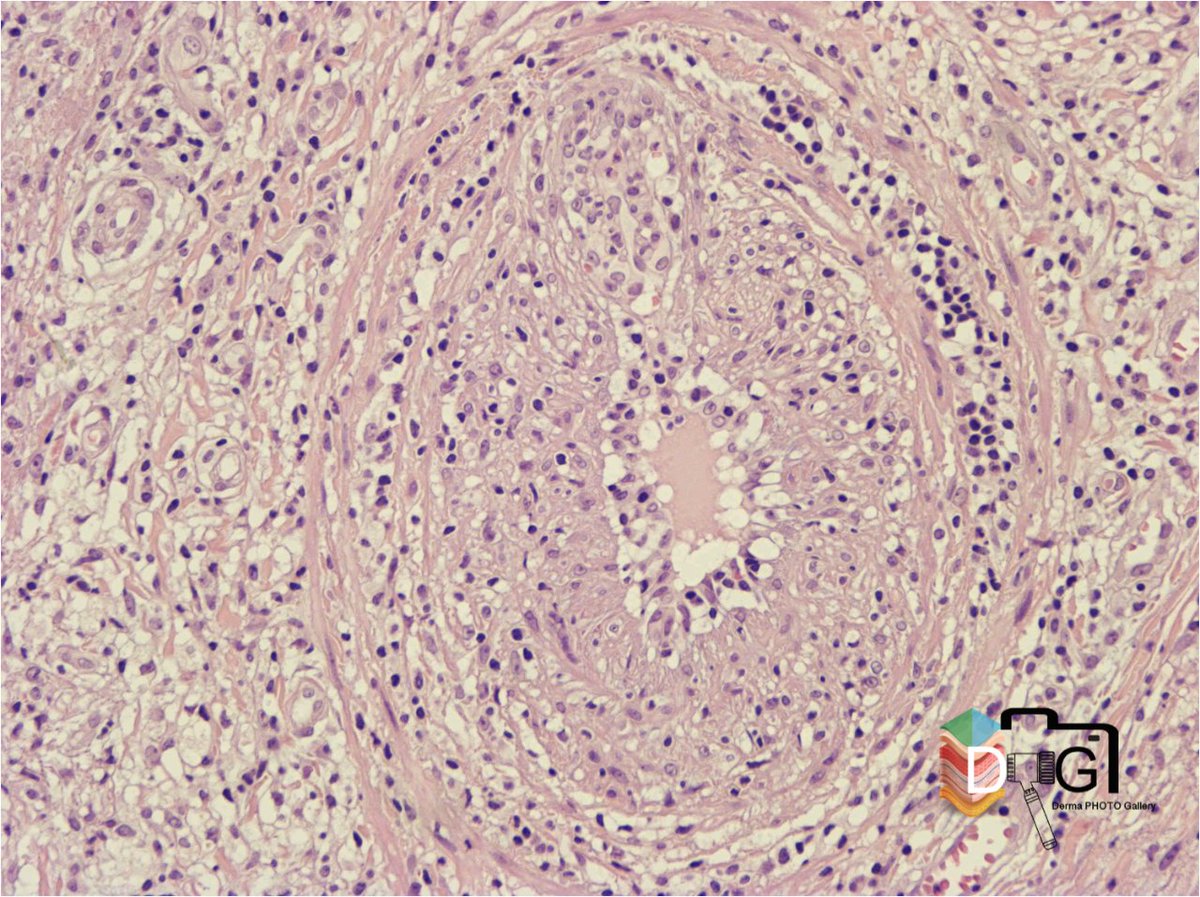

HISTOPATOLOGIA E INMUNOLOGIA DE LA LEPRA VII. 1/4

LEPRA TUBERCULOIDE SUBPOLAR (TTs). 1/2

Granulomas con signos activación epitelioide y menor circunscripción

Células gigantes tipo Langhans

Linfocitos con distribución + difusa respecto a macrófagos

Borramiento de la banda de Unna ImageImage

HISTOPATOLOGIA E INMUNOLOGIA DE LA LEPRA VII. 2/4

LEPRA TUBERCULOIDE SUBPOLAR (TTs). 2/2

Infiltrados liquenoides. Posible erosión epidérmica

Lesión neural importante

Los macrófagos de la lepra tuberculoide no expresan S-100

Marcada hiperplasia de células de Langerhans ImageImage